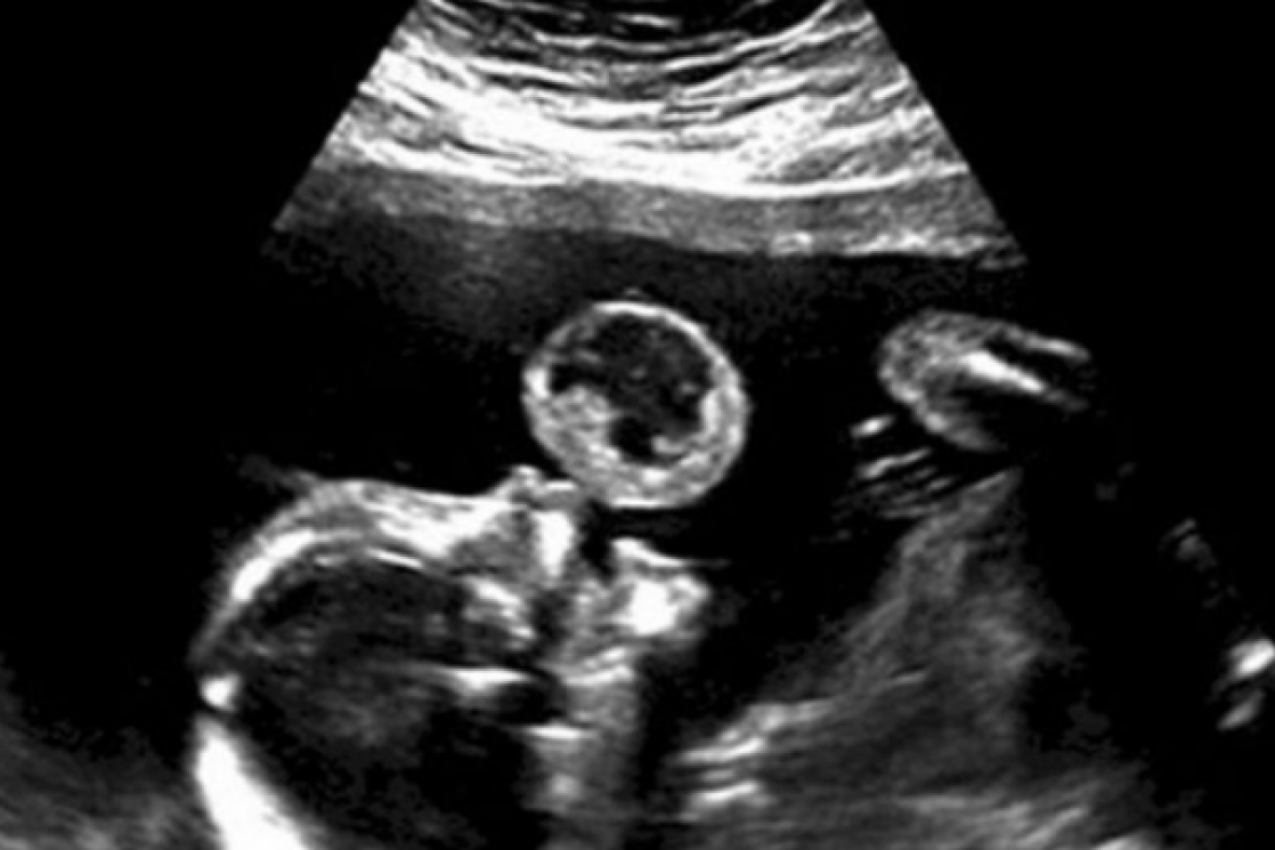

Jedan redovan ultrazvučni pregled promenio je sve za Tami Gonzalez, buduću majku koja je s nestrpljenjem čekala dolazak svoje bebe. Međutim, lekari su na snimku primetili nešto neuobičajeno. Naime, izgledalo je kao da beba duva balon. Dodatne analize otkrile su uzrok ovog neobičnog prizora. Reč je o oralnom teratomu, izuzetno retkom tumoru koji pogađa jedno od 100.000 novorođenčadi.

Teratom je tumor građen od raznovrsnih tkiva poreklom iz germinativne ćelije sa mogućnošću diferenciranja u tkiva iz sva tri razvojna embrionalna klicina lista (tridermom), pri čemu su tkiva i strukture više ili manje zreli. Najčešće je lokalizovan u polnim žlezdama (jajnici, testis), centralnom nervnom sistemu i telesnim šupljinama.